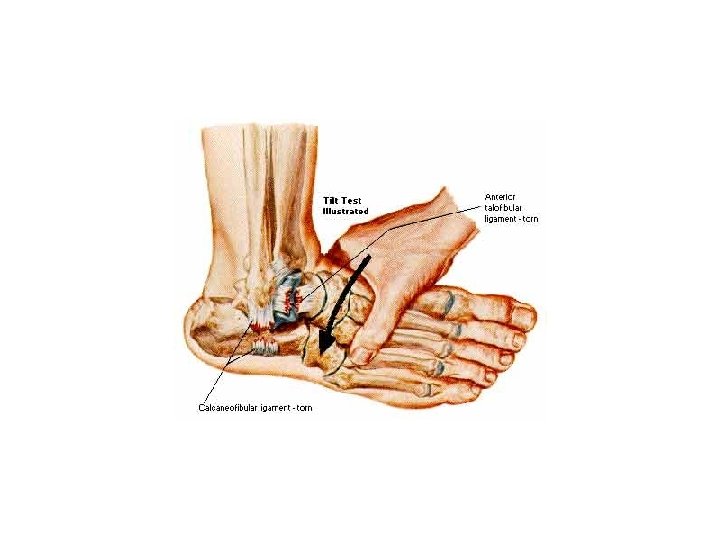

Anterior drawer tests should always be performed with the knee bent to eliminate the Achilles and Gastrocnemius muscles from providing any stability to the ankle. A lateral talar tilt test can be conducted at the same time.

Talar Tilt

Inversion Stress Test